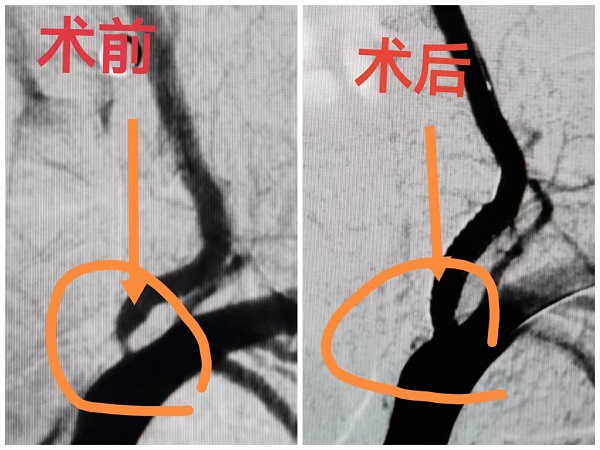

病例:患者男性,67岁,诊断“脑梗死、高血压、糖尿病、冠心病”,颈动脉彩超提示左侧颈动脉起始段狭窄,为进一步明确脑血管情况,预行脑血管造影;患者同时合并冠心病,提出希望能在脑血管造影同时,同台行冠脉造影明确心脏血管情况;为满足患者需求,我院神经内科立即请心血管内科医师会诊评估,最后决定为患者同台行冠脉及脑血管造影,造影顺利完成,精准评估了患者心脑血管狭窄程度,制定后期治疗计划,造影耗时约1.5小时,患者及家属非常满意。

脑血管支架治疗